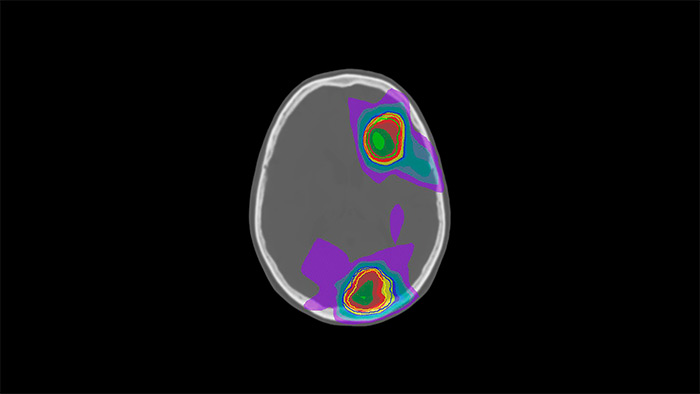

![MR Neuro Imaging]()

Damit mehr Patienten von der Magnetresonanztomographie profitieren, erfahren Sie hier mehr über neue neurologische Anwendungen von Philips Healthcare.